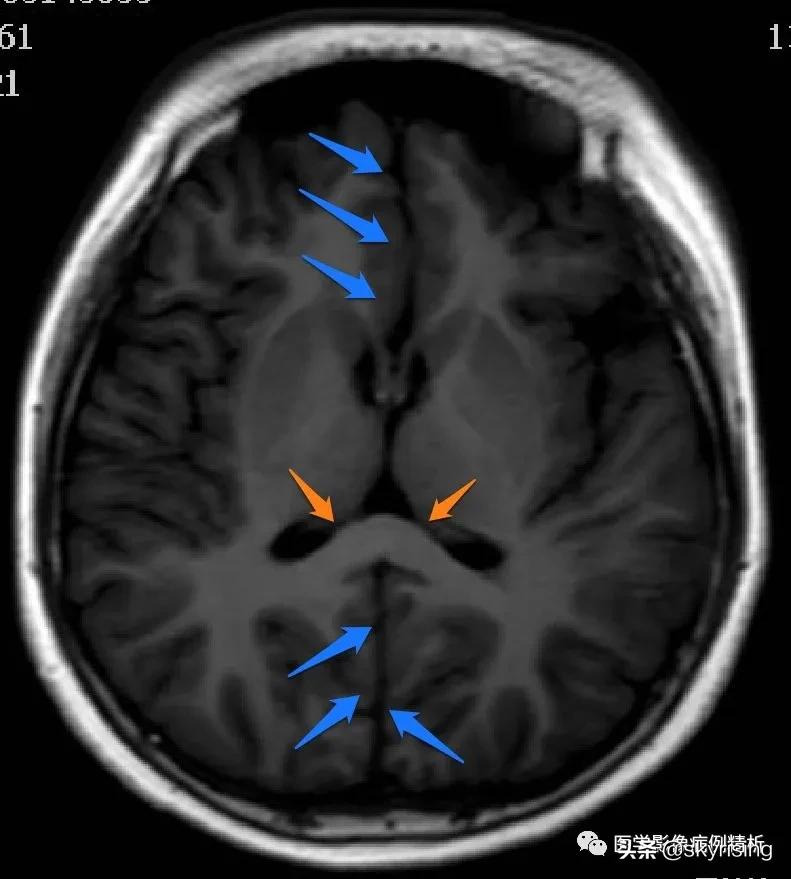

T1WI轴位像:黄色箭头所示可见大脑前纵裂缺如,双侧额叶脑实质融合,胼胝体膝部未见显示。透明隔缺如,双侧侧脑室融合呈蝙蝠翼样改变。侧脑室额角未见显示,体部平行于矢状线,后角失去张力、变尖。

黄色箭头所示为大脑前动脉单支血管影,被推移至融合脑实质前。枕角形态尚可。双侧额部蛛网膜下腔增宽,见细带状液体信号,提示硬膜下积液。

下图为正常成人基底节、侧脑室水平轴位T1WI图像。蓝色箭头为大脑纵裂,中间分离对称双侧大脑半球,黄色箭头为胼胝体膝部和压部,边缘为扣带回前后缘。